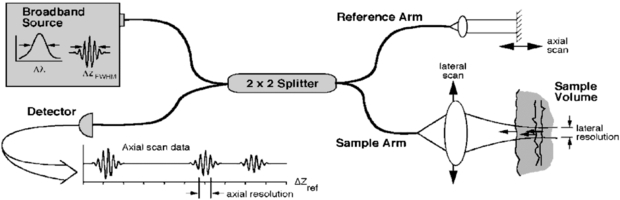

OCT is based on interferometry i.e. the interference between reflected light and a reference beam, which is used as a coherence gate to isolate light from specific depths. A Michelson interferometer is often used to perform the low-coherence interferometry for OCT (Fujimoto et al 2000). The frame rate for early OCT systems was typically 4 to 8 fps but faster modern systems are available at beyond video frame rate (depending on imaging parameters). A schematic representation of an OCT system is shown in figure 19 and example OCT B-mode image in figure 20.

Figure 19. Schematic of a time domain OCT instrument based on a fibre optic implementation of a Michelson interferometer. One arm of the interferometer is interfaced to the measurement instrument and the other arm has a scanning delay line. Reflections or backscattering from the object being imaged are correlated with light which travels the reference path. The envelope of the interference fringe signals yields the depth profile for the sample. In contrast, the interference fringe signals associated with the Fourier domain OCT are detected as a function of optical frequency (from Fujimoto et al 2000). These components can be miniaturized for adaptation to endoscopes or mounting in microscopes. (Permission to re-use granted by Thorlabs Ltd.)